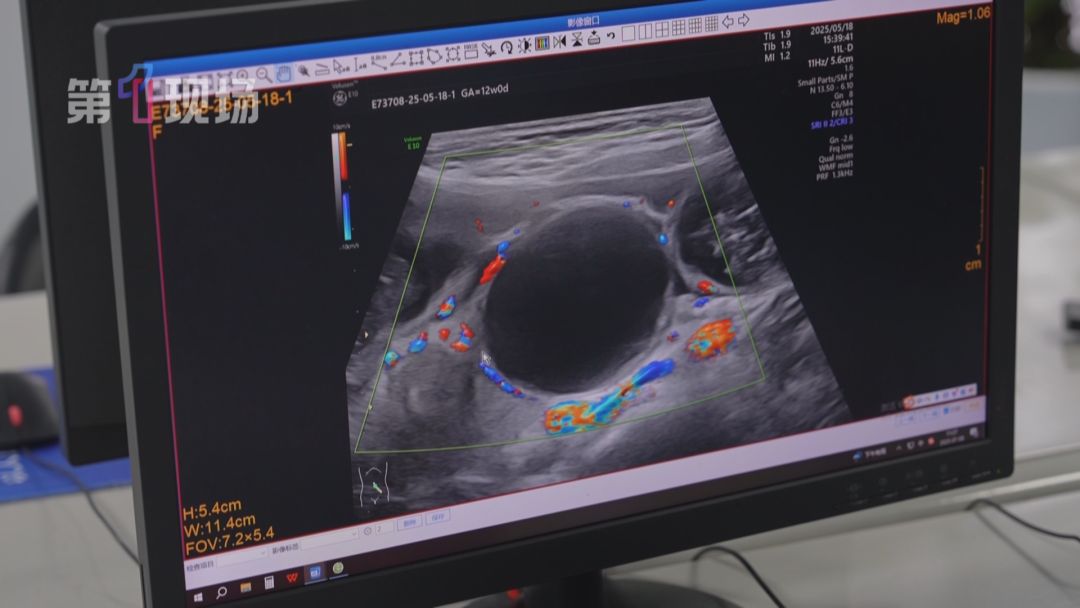

光明区人民医院超声医学科副主任医师李洲介绍,“水宝宝”在肠道长时间停留的话,会引起肠管的坏死,这是一个很严重的并发症。肠管黑色的部分,就是“水宝宝”膨胀堵在这里形成的,可以看到这个“水宝宝”已经泡得很大了。